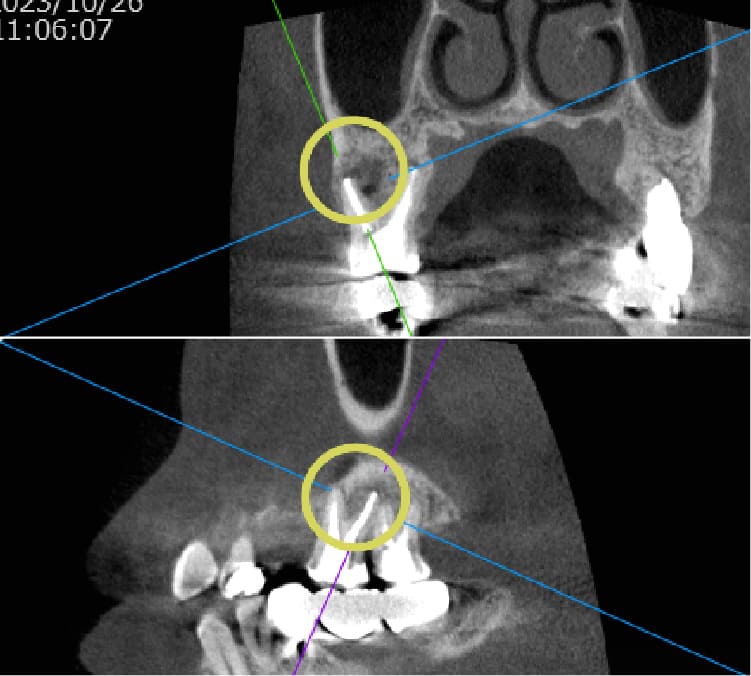

| 歯科用CTによる三次元診断 | 拡大ルーペの使用 |

| 一般的なレントゲン(二次元)では見えない、歯根の複雑な構造や病巣の位置を立体的に正確に把握し、治療の見落としを防ぎます。 | 肉眼では困難な根管内の細部を約8倍に拡大して確認し、処置の精度を高めます。 |

| 歯科用CTによる三次元診断 |

| 一般的なレントゲン(二次元)では見えない、歯根の複雑な構造や病巣の位置を立体的に正確に把握し、治療の見落としを防ぎます。 |